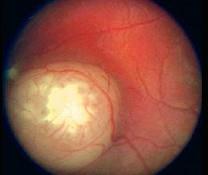

问题 以下关于视网膜母细胞瘤(如图)描述错误的是 ( )

选项 A、90%发生于3岁以前 B、男性多于女性 C、可出现钙化灶 D、是儿童最常见的原发性眼内恶性肿瘤 E、双眼发病约占30%~35%

答案 B